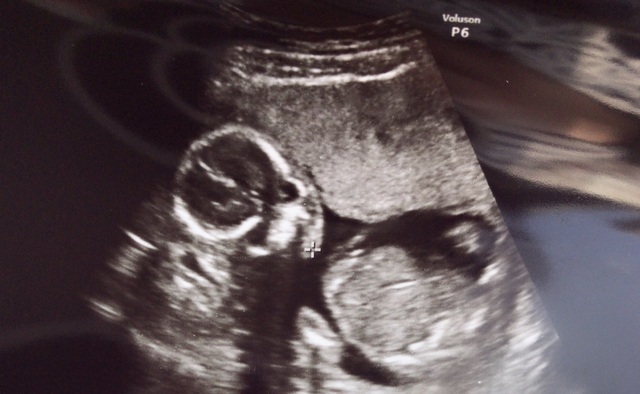

17週1日(17w1d・男の子)|みーぽんぽん さん(28歳)

エコー写真撮影時のエピソード:

初めてちゃんと顔を見せてくれたエコー写真です。顔はこのエコー写真しかなくて、他の写真はいつも手で隠してたので見られませんでした。

そんな中の貴重な顔の写真です!まだ男の子が女の子か分からない時期だったので、毎回診察の時、わくわくしながら見たのを覚えてます。